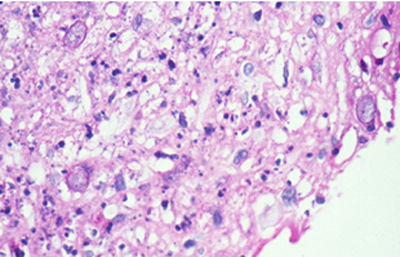

Cuando el examen patológico se realiza en cortes de tejido corneal procesados en parafina, (biopsias y discos de córnea de queratoplastias) las coloraciones que empleamos usualmente son la coloración de Hematoxilina-Eosina (Figura 49), el Blanco de Calcofluor. (Figura 50), la de PAS (Figura 51 y 52). De nuevo, la consideración de que una infección corneal puede ser causada por Acantamoebas es la condición indispensable en el diagnóstico diferencial para llegar a su diagnóstico

Fig. 49 H-E, Original x160